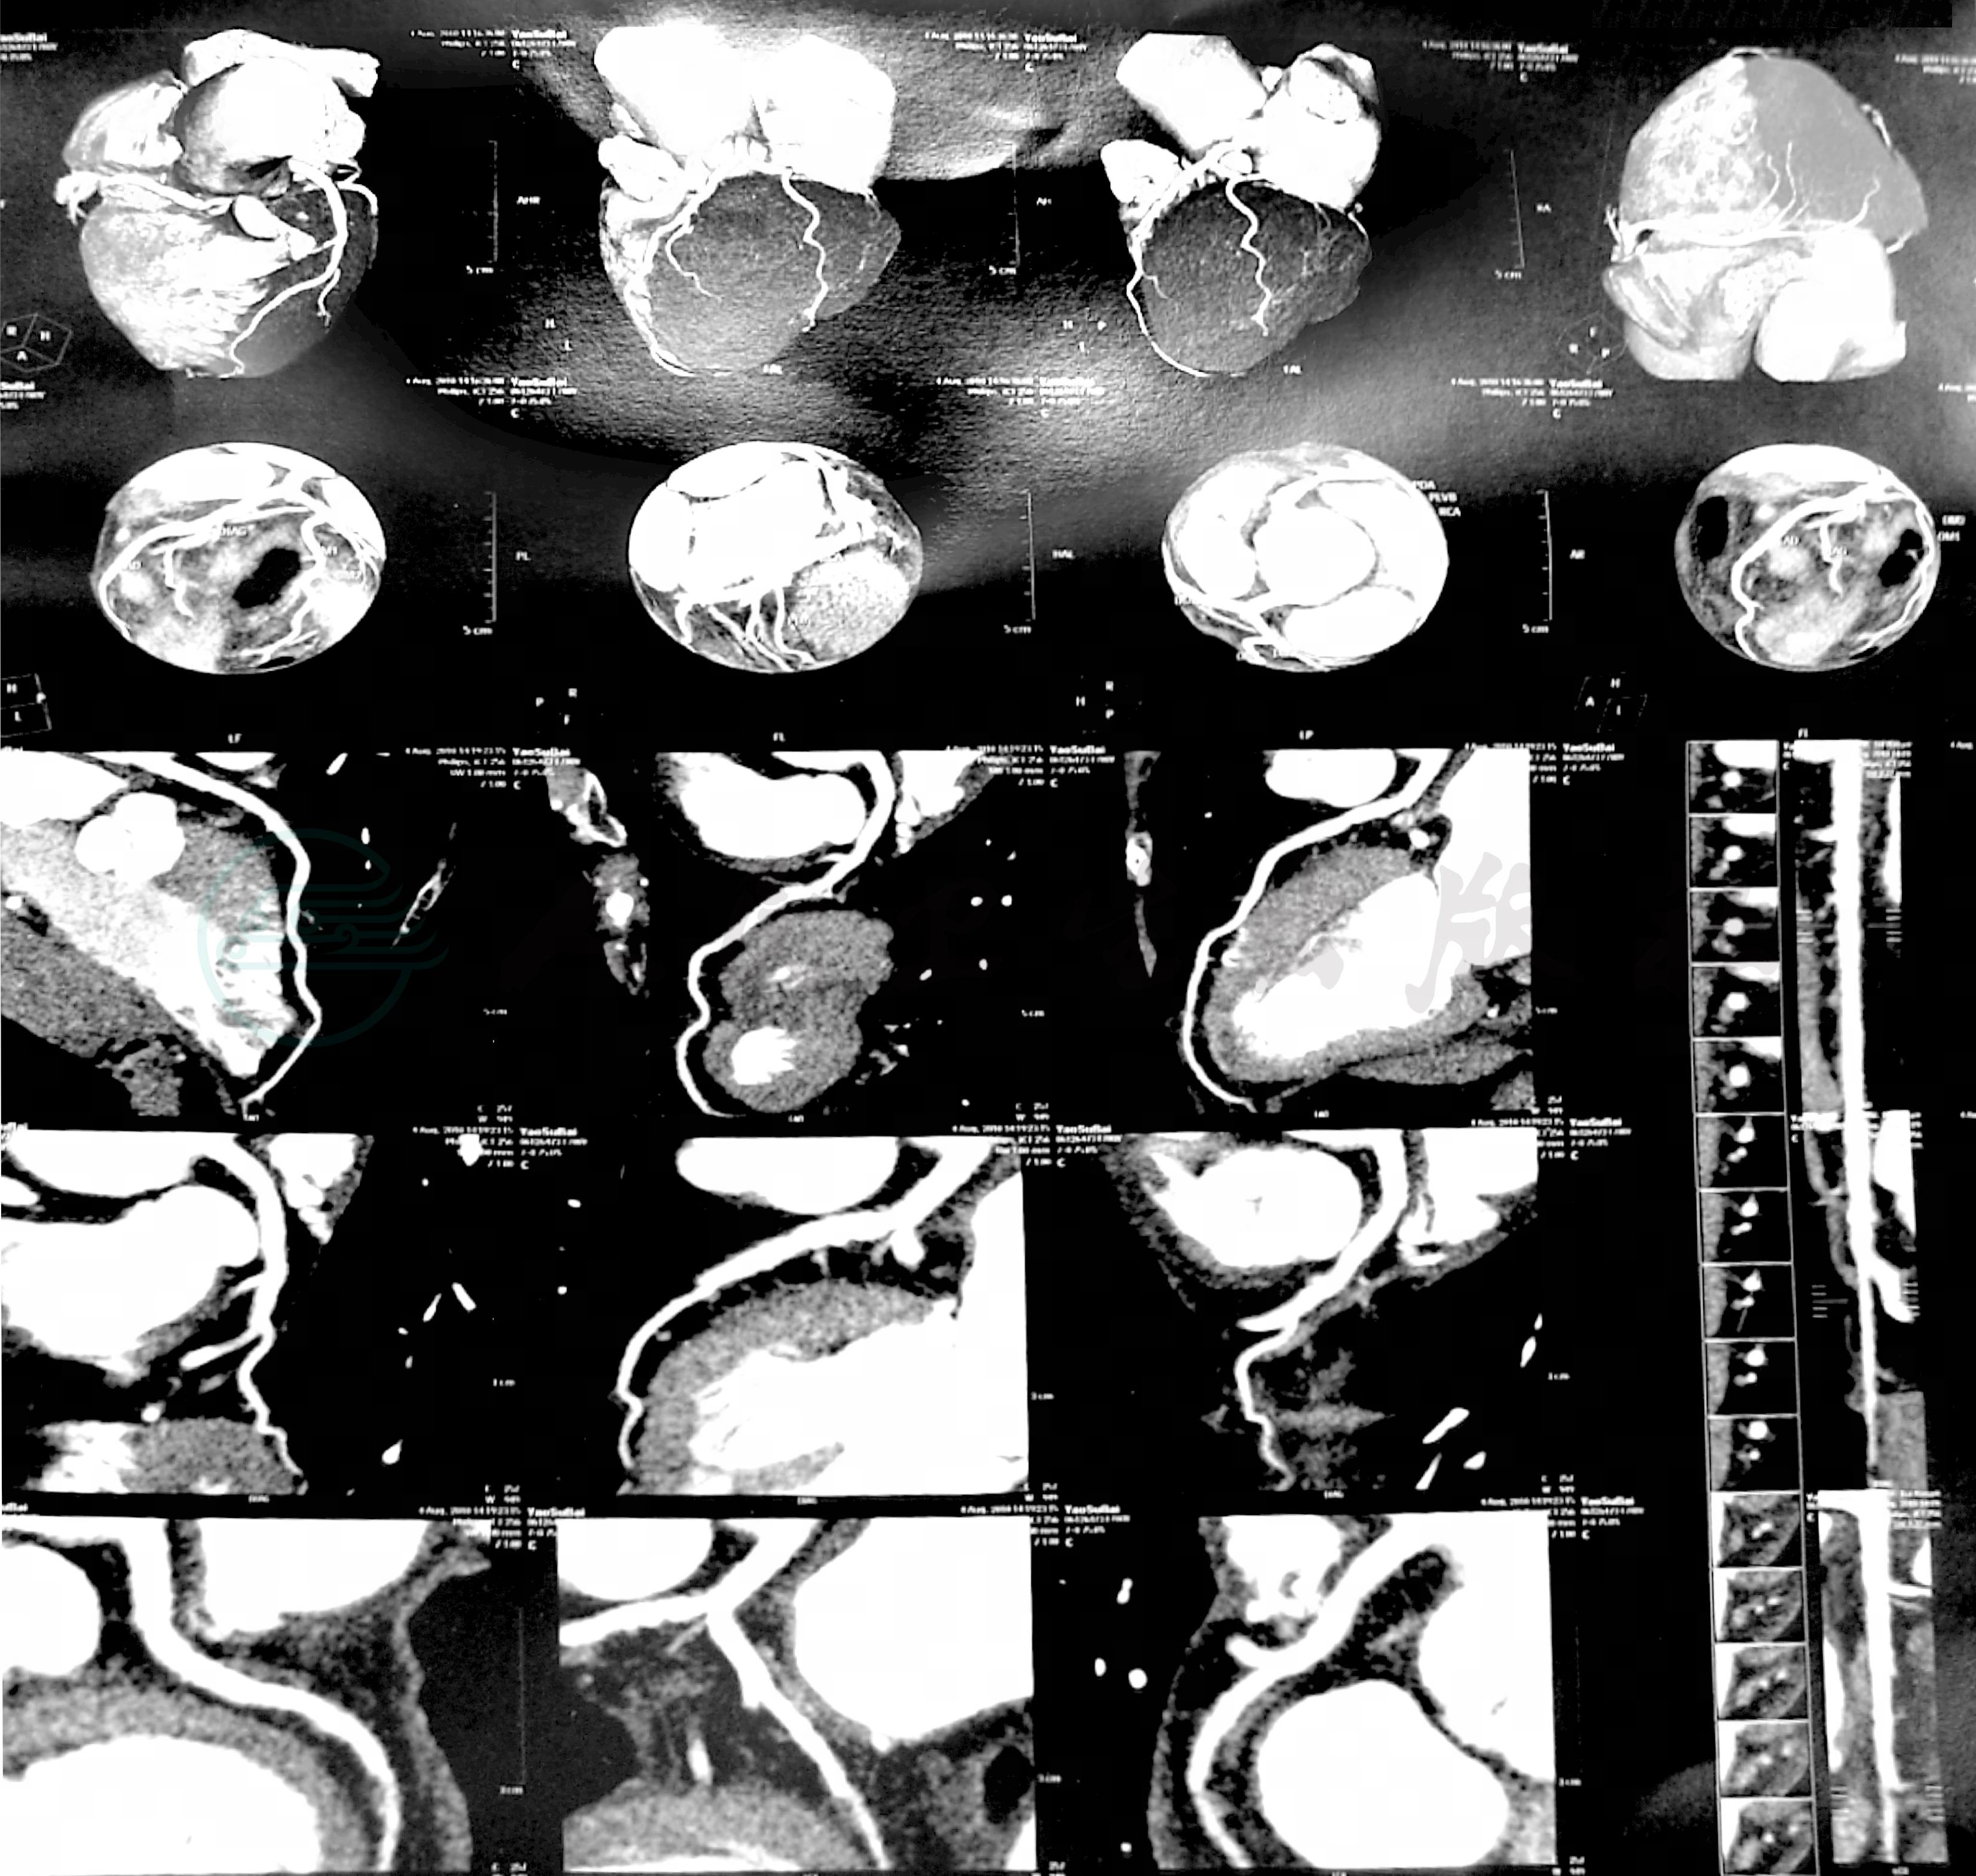

冠脉CT:两侧冠状动脉未见明显异常(图6、图7)。

图6 冠状动脉CT(2010年8月4日)

左冠:未见异常

图7 冠脉CT(2010年8月4日)

右冠:未见异常